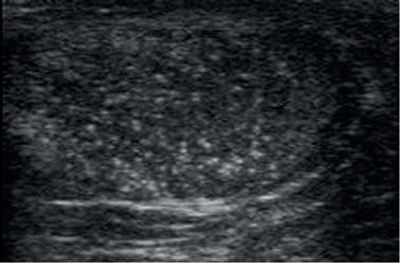

Testicular microlithiasis.

Testicular microlithiasis has a prevalence of about 5% in the general population. The incidence of testicular malignancy as a percentage of men with microlithiasis is 1% [2,3].

The prevalence of testicular microlithiasis in the sub-fertile population is 2.4%, and in this population men with testicular microlithiasis have a 4% incidence of testicular cancer [3].

Men who can be qualified by what is known as the testicular dysgenesis syndrome (TDS) should be considered for further investigation and treatment. These include men presenting with sub-fertility, history of cryptorchidism, testicular atrophy and unilateral testicular germ cell tumour (TGCT). Testicular microlithiasis has not been associated with an increased prevalence of intratubular germ cell neoplasia (ITGCN) in healthy asymptomatic men, but in those with the risk factors listed above. ITGCN is a premalignant lesion and is known to lead to TGCT [2,3,4].